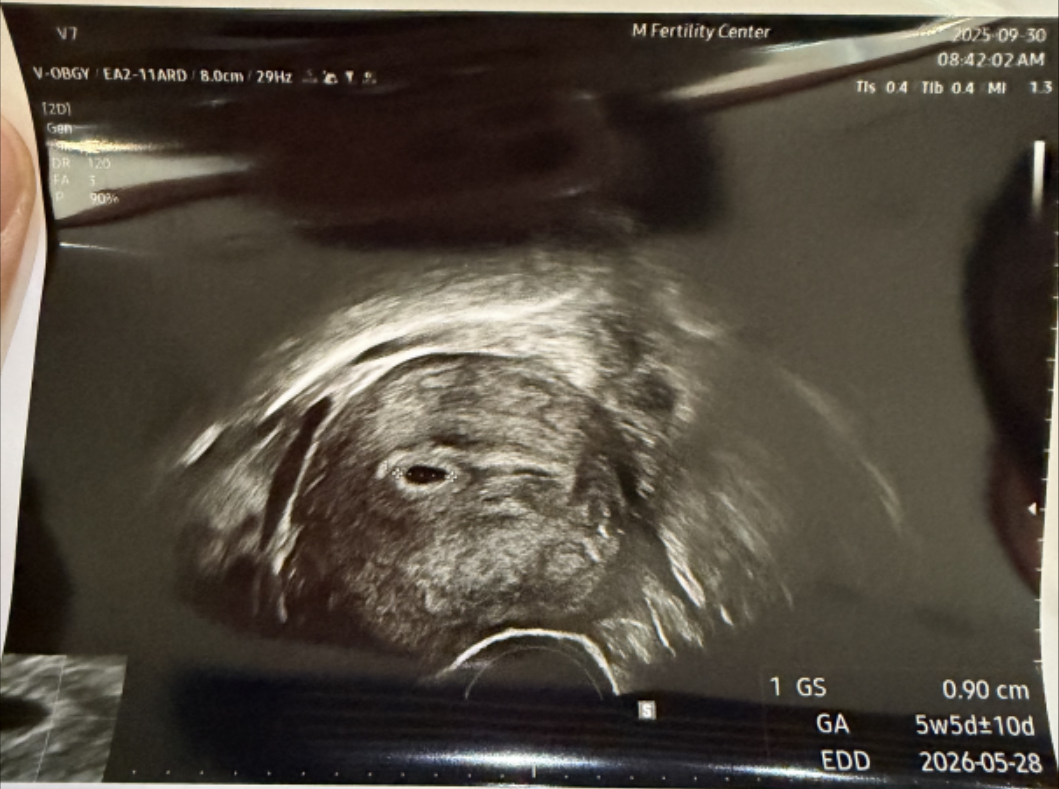

임신 5주 차(정확히는 5주 5일), 콩알만 한 0.9cm 아기집을 처음 확인한 날 우리 부부에게 아이가 생긴 것을 확인했다. 9월 13일 이식을 해서 9월 25일 더블링을 확인해 2주 남짓 지난 시점이었다. 임신 주수는 5주 차이며 출산 예정일은 다음 해인 26년 5~6월경이다. 나도 처음에는 어째서 이렇게 계산되는지 몰랐다. 생각보다 임신 주수는 길었으며 내가 생각한 10달 또한 엄청나게 … 더 읽기